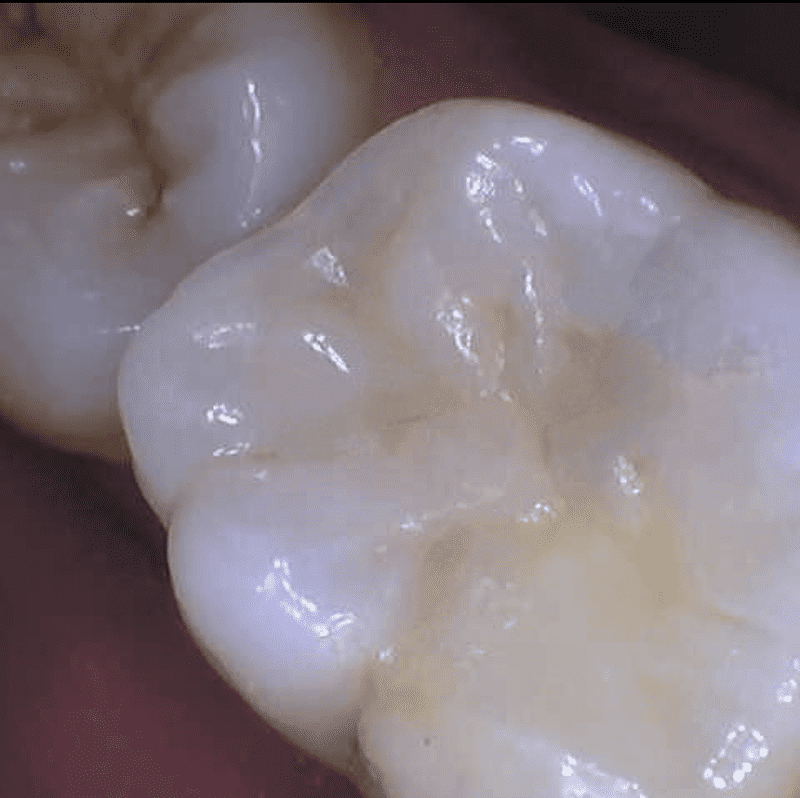

We offer state-of-the-art composite dental fillings in Leesburg, Virginia, as a core part of our comprehensive dental services. When cavities or tooth damage strike, composite fillings are a top-choice restorative solution, blending seamlessly with your natural teeth for both aesthetic and functional advantages.

- Aesthetic Appeal: These fillings are color-matched to your natural teeth, making them virtually indistinguishable. Say goodbye to unsightly metal fillings.

- Conservation of Tooth Structure: Composite fillings bond directly to the tooth, requiring minimal removal of healthy tooth structure. This ensures your tooth remains strong and durable.

- Application of the composite material in layers, each one carefully cured to ensure a solid bond.

- A final shaping and polishing to create a seamless appearance.